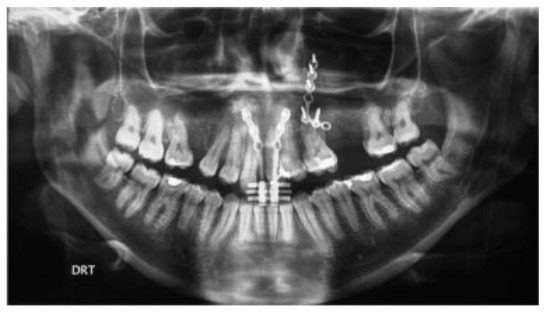

Immediate Reconstruction of Large Full-Thickness Segmental Anterior Maxillary Defect with Bone Transport

by Alberto Rocha Pereira, Nuno Montezuma, Luis Oliveira, Miguel Magalhães and José Rosa

Craniomaxillofac. Trauma Reconstr. 2016, 9(4), 305-312; https://doi.org/10.1055/s-0036-1592094 - 15 Sep 2016

Cited by 5

Abstract

Maxillary segmental defects are a reconstructive challenge particularly when the anterior arch is involved. Missing bone, mucosa, and teeth should be replaced; fistulae closure should be guaranteed by bone and mucosa continuity; stable functional occlusion should be achieved; and facial aesthetics restored. These [...] Read more.

Maxillary segmental defects are a reconstructive challenge particularly when the anterior arch is involved. Missing bone, mucosa, and teeth should be replaced; fistulae closure should be guaranteed by bone and mucosa continuity; stable functional occlusion should be achieved; and facial aesthetics restored. These defects resulting from tumor excisions, if left untreated, will cause additional problems related to interposed scar and collapse of lip and nose. Immediate reconstruction should avoid these problems and should be considered when safe tumor-free margins are obtained. This study describes the treatment of such a defect resulting from a myxoma excision, with trifocal distraction requiring only one additional surgery. Internal distractors were fixed bilaterally for transport of two segmental discs created by inverted L osteotomies at the same surgical time of tumor excision. A second surgery was performed after central contact between transport discs was achieved, for device removal and creation of a dynamic system to regenerate molding and compression-focus development. This was accomplished by internal fixation of one side and central fixation of a full-open distractor to act as compression device when reversely activated. Central perfect adaptation between transported segments and good-quality attached mucosa lining the alveolar crest were determinant to obtain a stable functional and aesthetic result. Full article

Show Figures

Figure 1